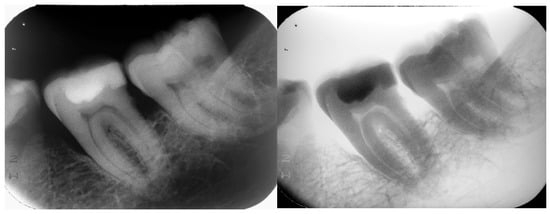

2.3. Radiologic Findings

The panoramic and intraoral radiographs revealed the internal structure of the atypical molar as well as the structure of neighboring teeth and anatomical features (Figure 4 and Figure 5). The intraoral radiographs were taken two months after the panoramic. There were no third molars in any of the quadrants. The atypical molar did not appear impacted and the surrounding cancellous bone exhibited a normal morphology, with no apparent pathologies. A mesial angular bone defect was identified in the proximal surface of the molar located distally of the second premolar, as well as a mild mesial tilting of this molar and an increased distance between its mesial root and the root of the second premolar. Horizontal bone loss was noticed between the two molars.

The atypical molar had three distinct roots, directed parallel to each other and separated by normal interradicular bone: a mesial root, a distal root and a middle root. The mesial root was the longest and the distal the shortest (as depicted in the 2D image). All roots were slightly inclined distally. The periodontal ligament space and lamina dura of the molar roots were visible and within normal limits. Two pulp chambers (the mesial and the distal) and three root canals (each root had one root canal) were visible. The mesial pulp chamber extended to the mesial and middle root canals and the distal pulp chamber to the distal root canal. The crown of the molar appeared to be divided in two unequal halves by a vertical radiopaque thin zone extending from the occlusal surface—as a continuation of the occlusal enamel, also exhibiting enamel radiopacity—to the cervical area of the middle root.

When considering the possibility of gemination—apparently involving an attempted division of the third molar in this case—the morphology of the irregular tooth is not entirely consistent with the characteristic features of this anomaly. The crown of the tooth appears to be composed of two unevenly sized smaller crowns arranged in continuity, whereas in gemination, the two halves of the joined crown typically present as mirror images [7,23]. Radiographically, three roots are depicted, and the pulp chamber of the tooth seems to be divided into two distinct pulp chambers, separated by a vertical thin radiopaque septum. This feature is more apparent in the original and reversed intraoral radiographs. However, as the literature suggests, geminated teeth result in a single root chamber and root canal [7,12], and moreover, gemination is more common in the anterior maxillary region [33] and is extremely rare in molars. An exceptionally rare case of a geminated mandibular third molar was recently reported by Brauer & Bartols (2023), where the tooth crown was enlarged, resembling two teeth, and it had several roots with a continuous pulp [34].

Concrescence may be considered a potential diagnosis for the present tooth anomaly, assuming the presence of a supernumerary fourth molar. Indeed, Gunduz et al. (2006) have reported a case of the concrescence of a mandibular third molar and a supernumerary fourth molar [25]. This interpretation seems to be supported by the radiographic image, which reveals an area of cementum fusion apical to the enamel septum, at the site where the two teeth appear to unite. However, in addition to its rare occurrence in the mandible, concrescence is characterized by the fusion of only the roots of two adjacent teeth, with interdental bone breakdown [8,25,34].

Fusion between the third molar and a fourth supernumerary molar could be proposed as a plausible diagnosis, also supported by the clinical and radiographic findings. Despite the fact that supernumerary molars are rare conditions, reported to have a prevalence of 0.26–2%, with a much higher propensity for the maxilla [35,36], a number of cases of fusion between mandibular third and fourth molars have been reported [15,16,18,25]. The clinical appearance of the irregular tooth, depicting eight cusps, is consistent with the union of two molars, a larger one (third molar) and a smaller one (supernumerary fourth molar). Radiographically, the two teeth are separated/united by a thin enamel septum, representing the union of two completely separate tooth germs, as happens in fusion. The fused tooth presents two separate pulp chambers, of which the one located in the larger crown extends to two root canals into the two roots, and the other pulp chamber located in the smaller crown extends to one root canal into the third root. The three roots aligned in parallel may represent the two roots of the third molar joined to the single root of the supernumerary fourth molar. It is worth noting that the number of roots visible on the 2D radiographs may not reflect the actual number, as studies have reported a statistically significant difference, with more roots detected in extracted third molars compared to those observed on the respective panoramic images [27].

Figure 5. Intraoral periapical radiograph (original and reversed image).